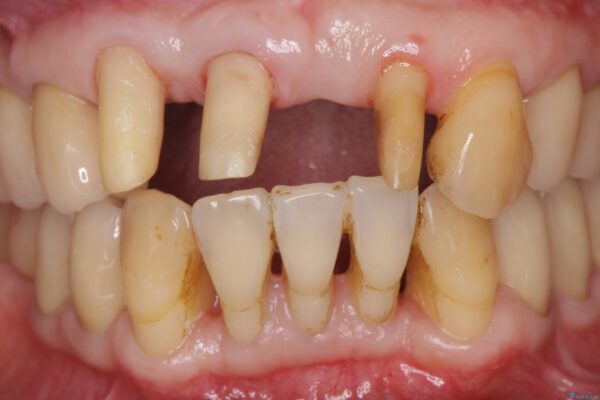

治療前

歯の総合的なマネージメントを行う包括的歯科治療の実践[ 歯周病・矯正・セラミック補綴 ] 治療前画像 歯の総合的なマネージメントを行う包括的歯科治療の実践[ 歯周病・矯正・セラミック補綴 ] 治療前画像 歯の総合的なマネージメントを行う包括的歯科治療の実践[ 歯周病・矯正・セラミック補綴 ] 治療前画像 歯の総合的なマネージメントを行う包括的歯科治療の実践[ 歯周病・矯正・セラミック補綴 ] 治療前画像 歯の総合的なマネージメントを行う包括的歯科治療の実践[ 歯周病・矯正・セラミック補綴 ] 治療前画像 歯の総合的なマネージメントを行う包括的歯科治療の実践[ 歯周病・矯正・セラミック補綴 ] 治療前画像 歯の総合的なマネージメントを行う包括的歯科治療の実践[ 歯周病・矯正・セラミック補綴 ] 治療前画像